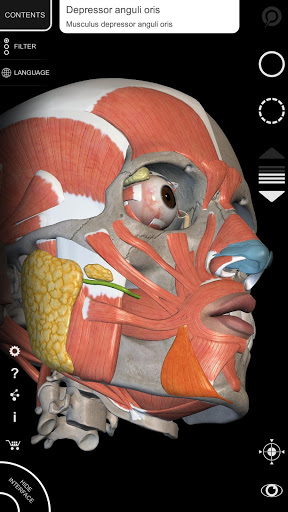

"Anatomy 3D Atlas" дозволяє легко та інтерактивно вивчати анатомію людини.

Завдяки простому та інтуїтивно зрозумілому інтерфейсу можна спостерігати кожну анатомічну структуру під будь-яким кутом.

Анатомічні 3D-моделі особливо деталізовані та мають текстури з роздільною здатністю до 4k.

Поділ за регіонами та попередньо визначені види полегшують спостереження та вивчення окремих частин або груп систем і зв’язків між різними органами.

• Візуалізація м’язів через рівні шарів від поверхневих донизу до найглибших

• Вибравши модель або шпильку, з’явиться відповідний анатомічний термін

• Опис м’язів: походження, приєднання, іннервація та дія